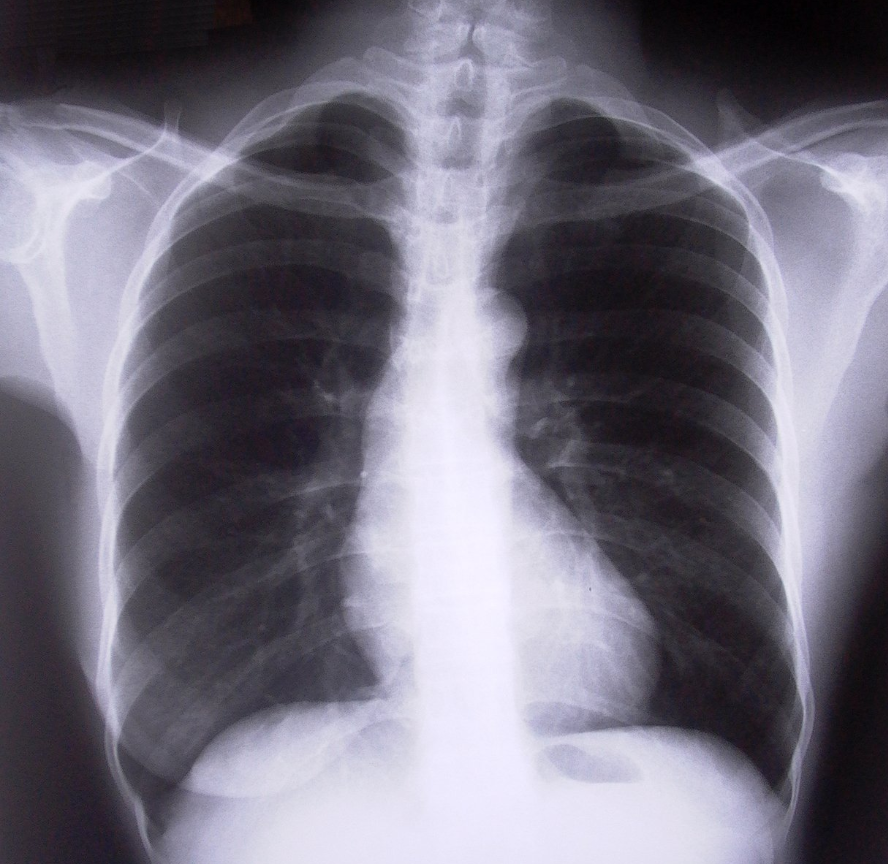

Silica & Asbestos Medical Surveillance regulations require chest films for silicosis and asbestos. The films must be read by one of a "B Reader", a radiologist with specialized training.